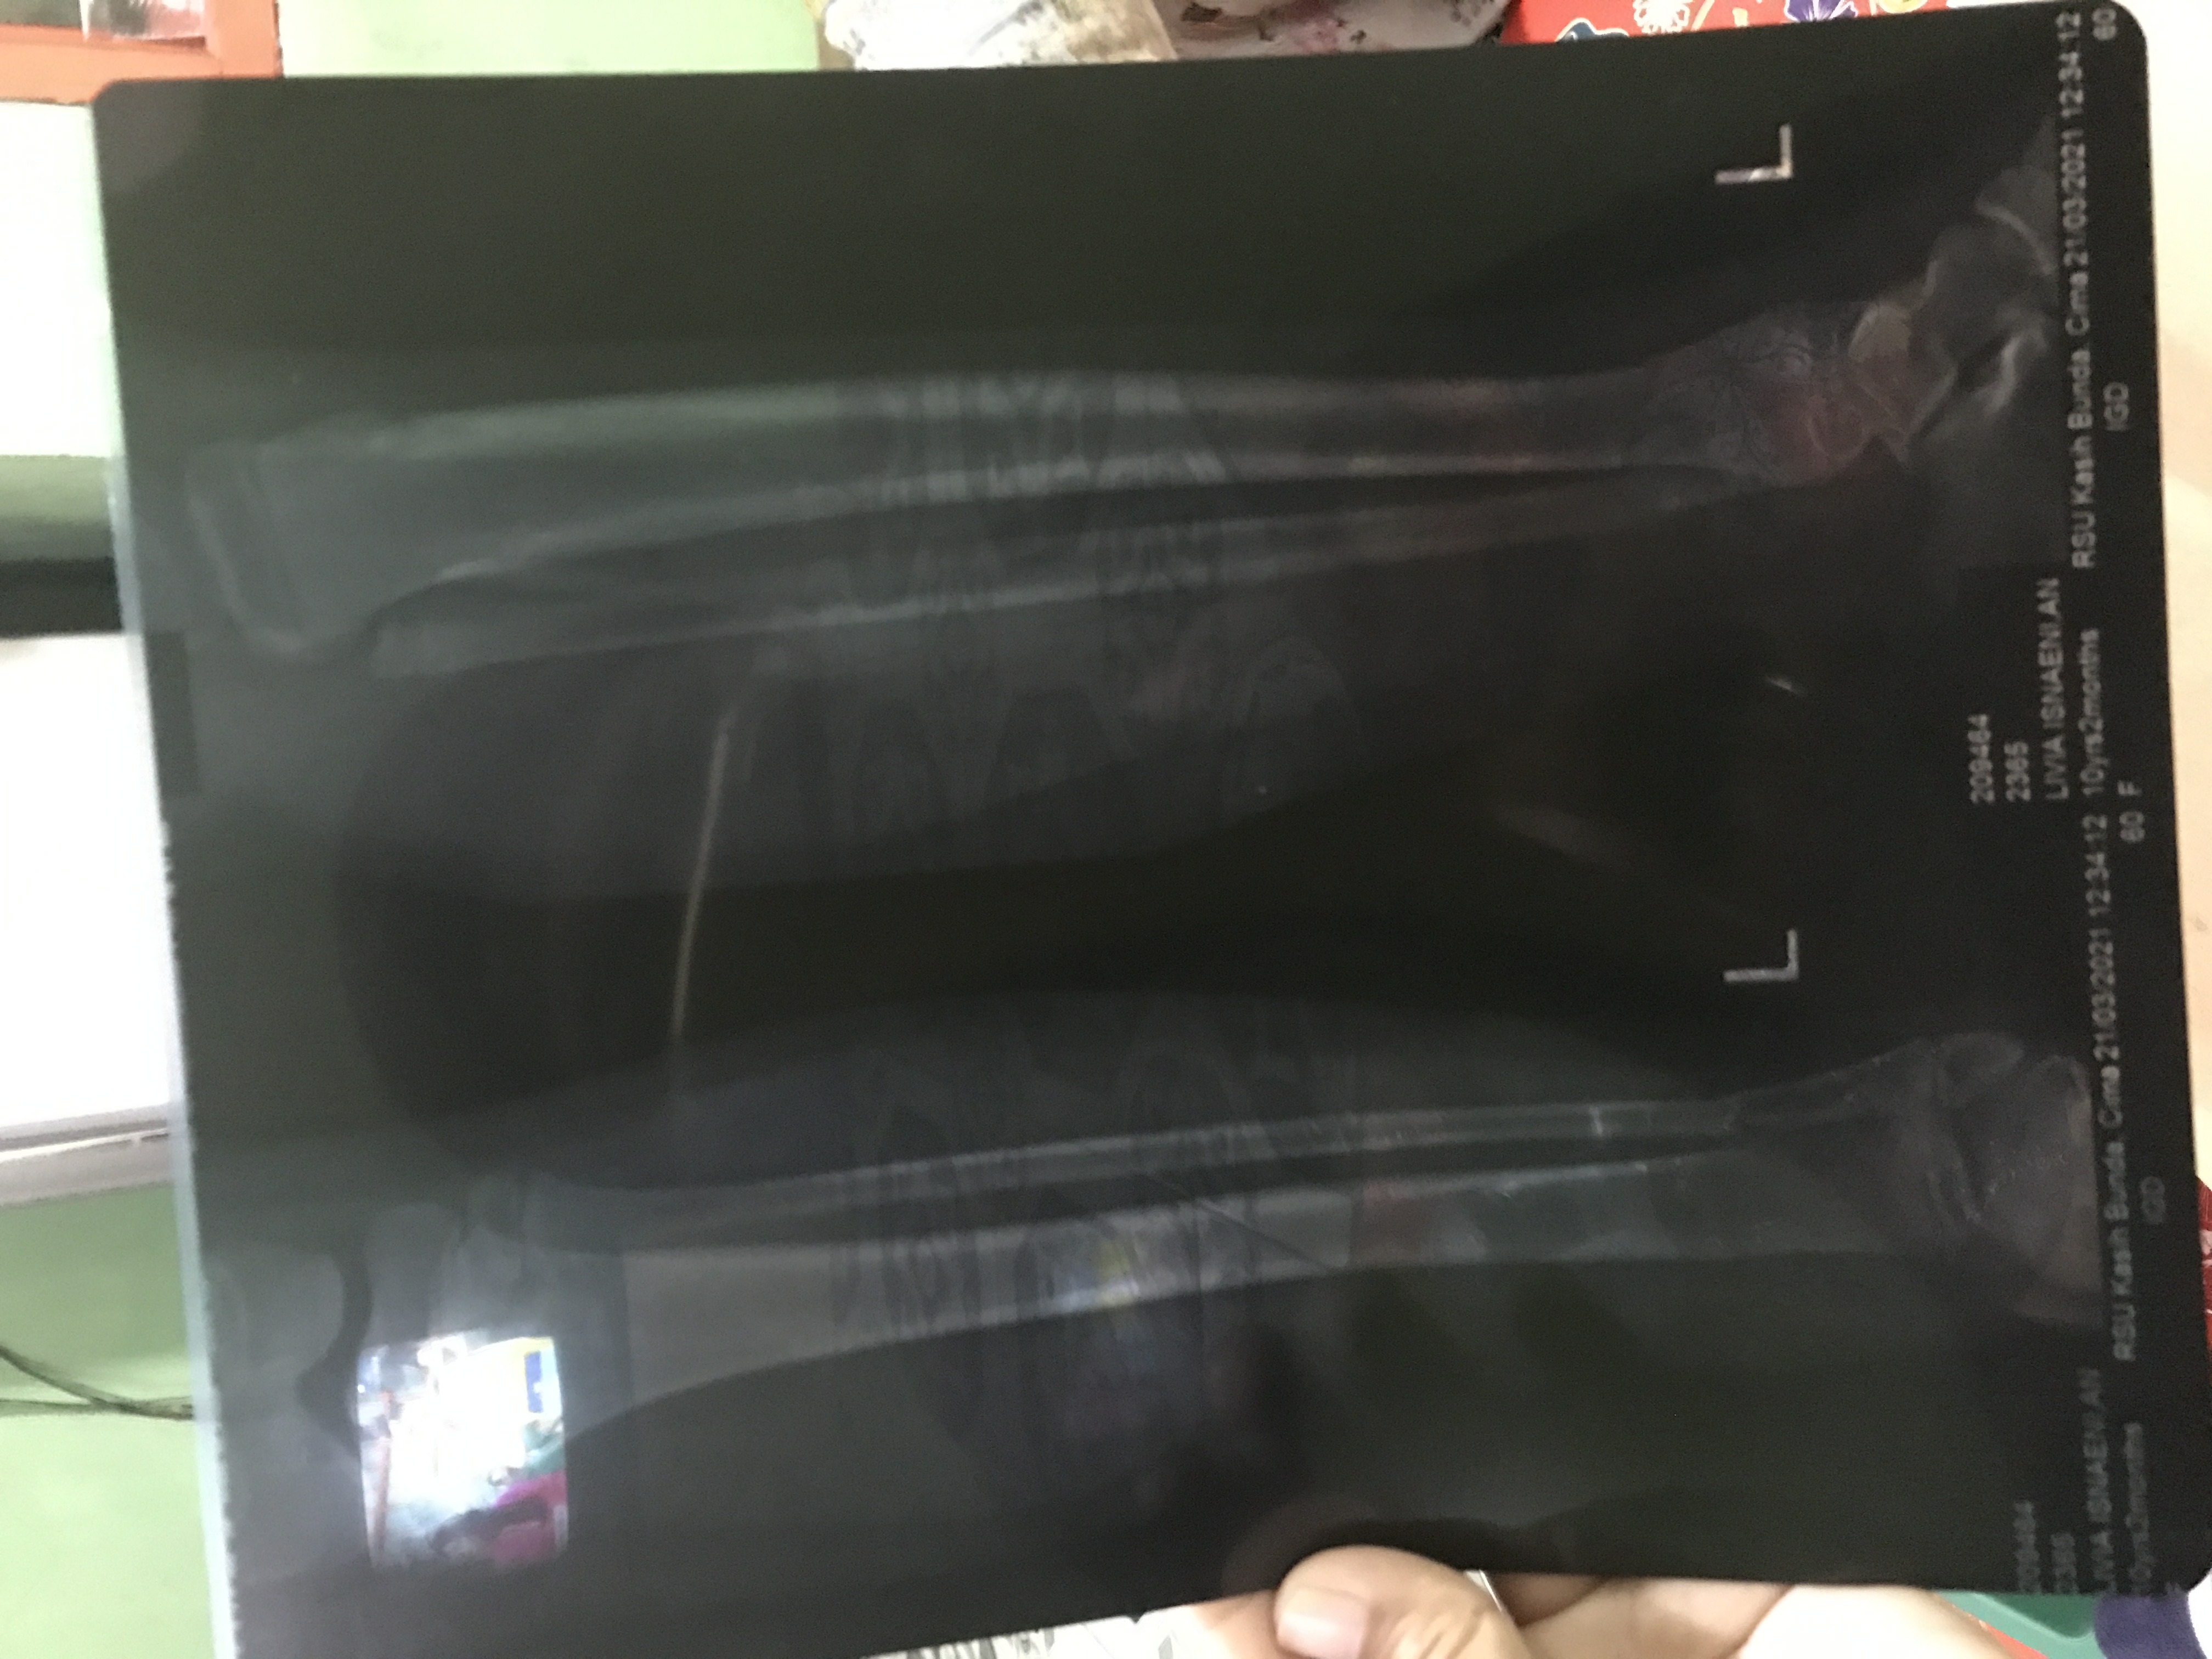

Namun seketika acara tersebut menjadi peristiwa tak terlupakan. Tiba-tiba pondasi beton runtuh menimpa Livia yang saat itu sedang dipangku oleh Ibunya. Peristiwa itu menyebabkan kaki Livia patah dan harus dilarikan ke Rumah Sakit untuk mendapatkan pertolongan.

Alhamdulillah Livia dapat ditangani dan menjalani operasi pemasangan pen. Saat ini kondisi Livia hanya bisa terbaring di tempat tidur di rumahnya.